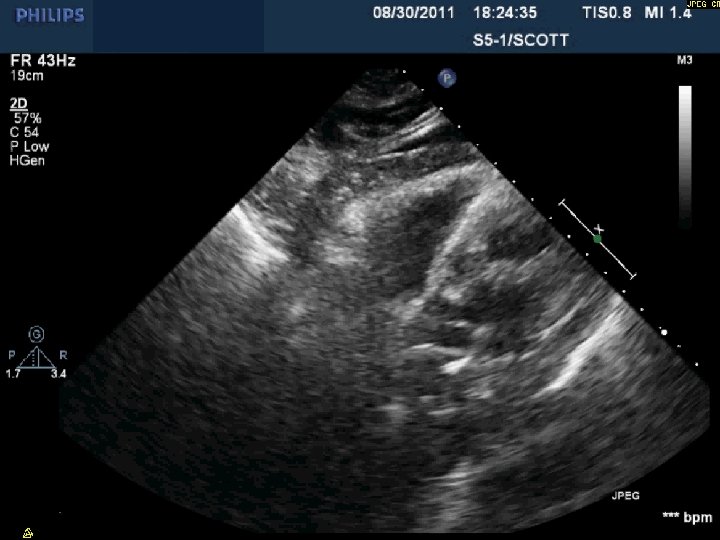

Day 2 No further pericardial drainage, echo without effusion…pericardial catheter pulled Day 3 Enoxaparin

Day 2 No further pericardial drainage, echo without effusion…pericardial catheter pulled Day 3 Enoxaparin for DVT prophylaxis initiated 8 hours later, PEA arrest Echo shows recurrence of effusion and tamponade physiology